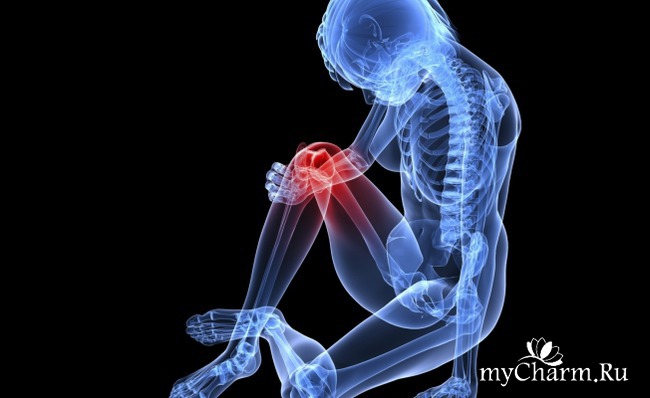

10 важных фактов о ваших костях

Кости состоят из минералов таких, как фосфор и кальций, белков, коллагена, а также живых клеток. Хотя кости после определенного момента уже перестают расти, но старые клетки костей постепенно разрушаются и меняется на новые. Но защитить ваши кости от некоторых факторов риска остеопороза - слабости и хрупкости костей - вполне реально. Вот несколько полезных фактов о костях:

Наши кости даны нам на всю жизнь, но гормоны и различные лекарственные препараты, неправильное питание могут разрушить их прочность. Сохранять силу и здоровые костей, данных человеку с детства - настоящий труд. Для этого будет полезным узнать несколько важных фактов о костях. Кости состоят из минералов таких, как фосфор и кальций, белков, коллагена, а также живых клеток... Читать полностью |